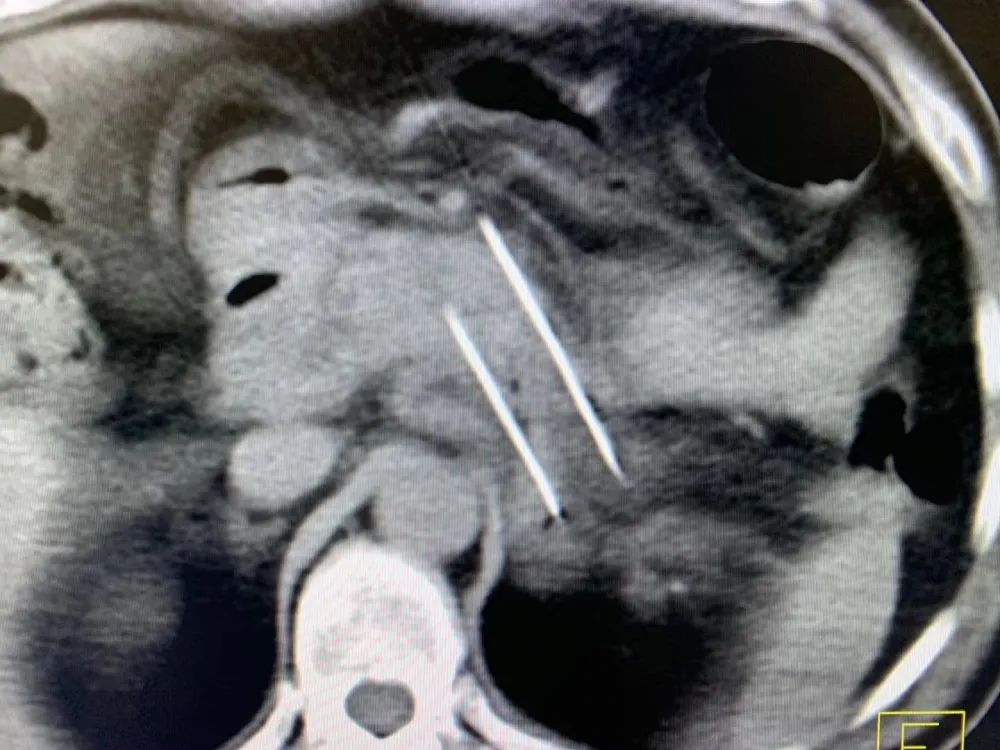

6月2日上午10點,主刀醫(yī)生牛立志院長在全麻下為他進行納米刀消融手術(shù),在CT和B超引導(dǎo)下進行腹腔鏡納米刀消融,納米刀消融技術(shù)是一種全新的腫瘤微創(chuàng)消融技術(shù),其原理是利用電極探針產(chǎn)生的高壓電脈沖,使腫瘤細(xì)胞膜上發(fā)生不可逆納米級穿孔,破壞腫瘤細(xì)胞內(nèi)外平衡,從而令腫瘤細(xì)胞凋亡。手術(shù)持續(xù)近兩個小時順利結(jié)束。